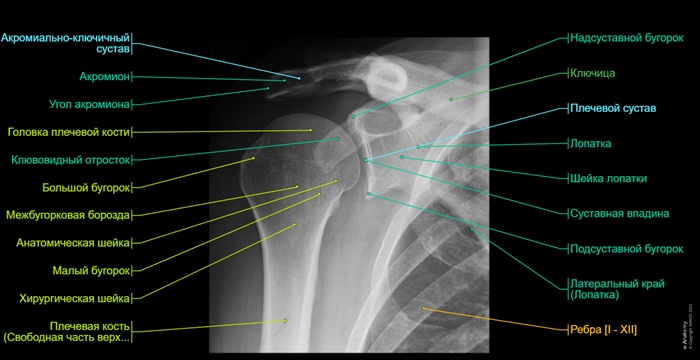

Для снимка в прямой проекции пациент садится боком к экрану аппарата. Рука отводится в сторону, выпрямляется в локте и укладывается на плоскость рентгеновского прибора (ладонь вверх). Это положение позволяет сделать наиболее подробный снимок костей плечевого пояса.

Расшифровка снимков рентгенографии плеча

При расшифровке снимка врач смотрит на потемнения, тени, структуру кости и на основании исследования пишет заключение.

В норме должны четко просматриваться контуры плечевой кости (без разрывов). Не должно быть затемнений, новообразований, отростков.